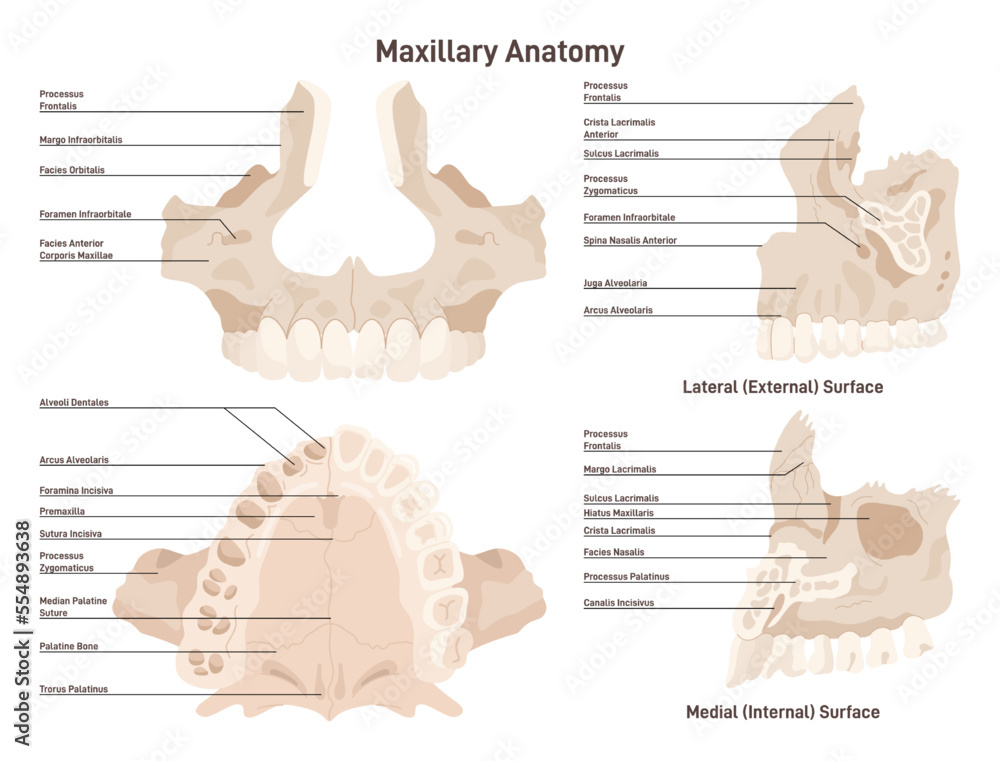

Discover the sophistication of annotated illustration of the jaw's anatomy | stable diffusion online with our curated gallery of numerous images. featuring elegant examples of photography, images, and pictures. ideal for luxury lifestyle publications. Browse our premium annotated illustration of the jaw's anatomy | stable diffusion online gallery featuring professionally curated photographs. Suitable for various applications including web design, social media, personal projects, and digital content creation All annotated illustration of the jaw's anatomy | stable diffusion online images are available in high resolution with professional-grade quality, optimized for both digital and print applications, and include comprehensive metadata for easy organization and usage. Our annotated illustration of the jaw's anatomy | stable diffusion online gallery offers diverse visual resources to bring your ideas to life. Professional licensing options accommodate both commercial and educational usage requirements. Cost-effective licensing makes professional annotated illustration of the jaw's anatomy | stable diffusion online photography accessible to all budgets. Regular updates keep the annotated illustration of the jaw's anatomy | stable diffusion online collection current with contemporary trends and styles. Multiple resolution options ensure optimal performance across different platforms and applications. Time-saving browsing features help users locate ideal annotated illustration of the jaw's anatomy | stable diffusion online images quickly. Whether for commercial projects or personal use, our annotated illustration of the jaw's anatomy | stable diffusion online collection delivers consistent excellence.